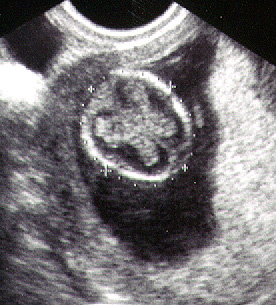

يصبح الجنين في نهاية هذا الأسبوع حوالي 3.75 سم وحوالي 9.3 جرام. بالنسبة للجفون فهي ملتحمة مع العين وتبقي هكذا حتى الأسبوع السابع والعشرين. يستمر المعصم في النمو هذا الأسبوع ويتكون الكاحل وتبدأ أصابع اليد والقدم في الظهور ويزداد طول الأذرع.

ينتهي التكوين الداخلي للأذن في نهاية هذا الأسبوع. بالرغم من عدم إمكانية تحديد نوع الجنين (ذكر أم أنثي) في هذا الوقت عن طريق الموجات فوق الصوتية ولكن تبدأ الأعضاء التناسلية في التكوين هذا الأسبوع.

وتكتمل المشيمة الآن وتبدأ في القيام بوظائفها كاملة وأهمها إفراز الهرمون. بالنسبة للسيدات فوق سن 35 أو إذا كان هناك تاريخ مرضي للعائلة له علاقة بالأمراض الوراثية، فيجب القيام بعمل فحوصات طبية ما بين الأسبوع الأول والعاشر والتي تحدد إذا كان هناك أي نمو غير طبيعي للجنين